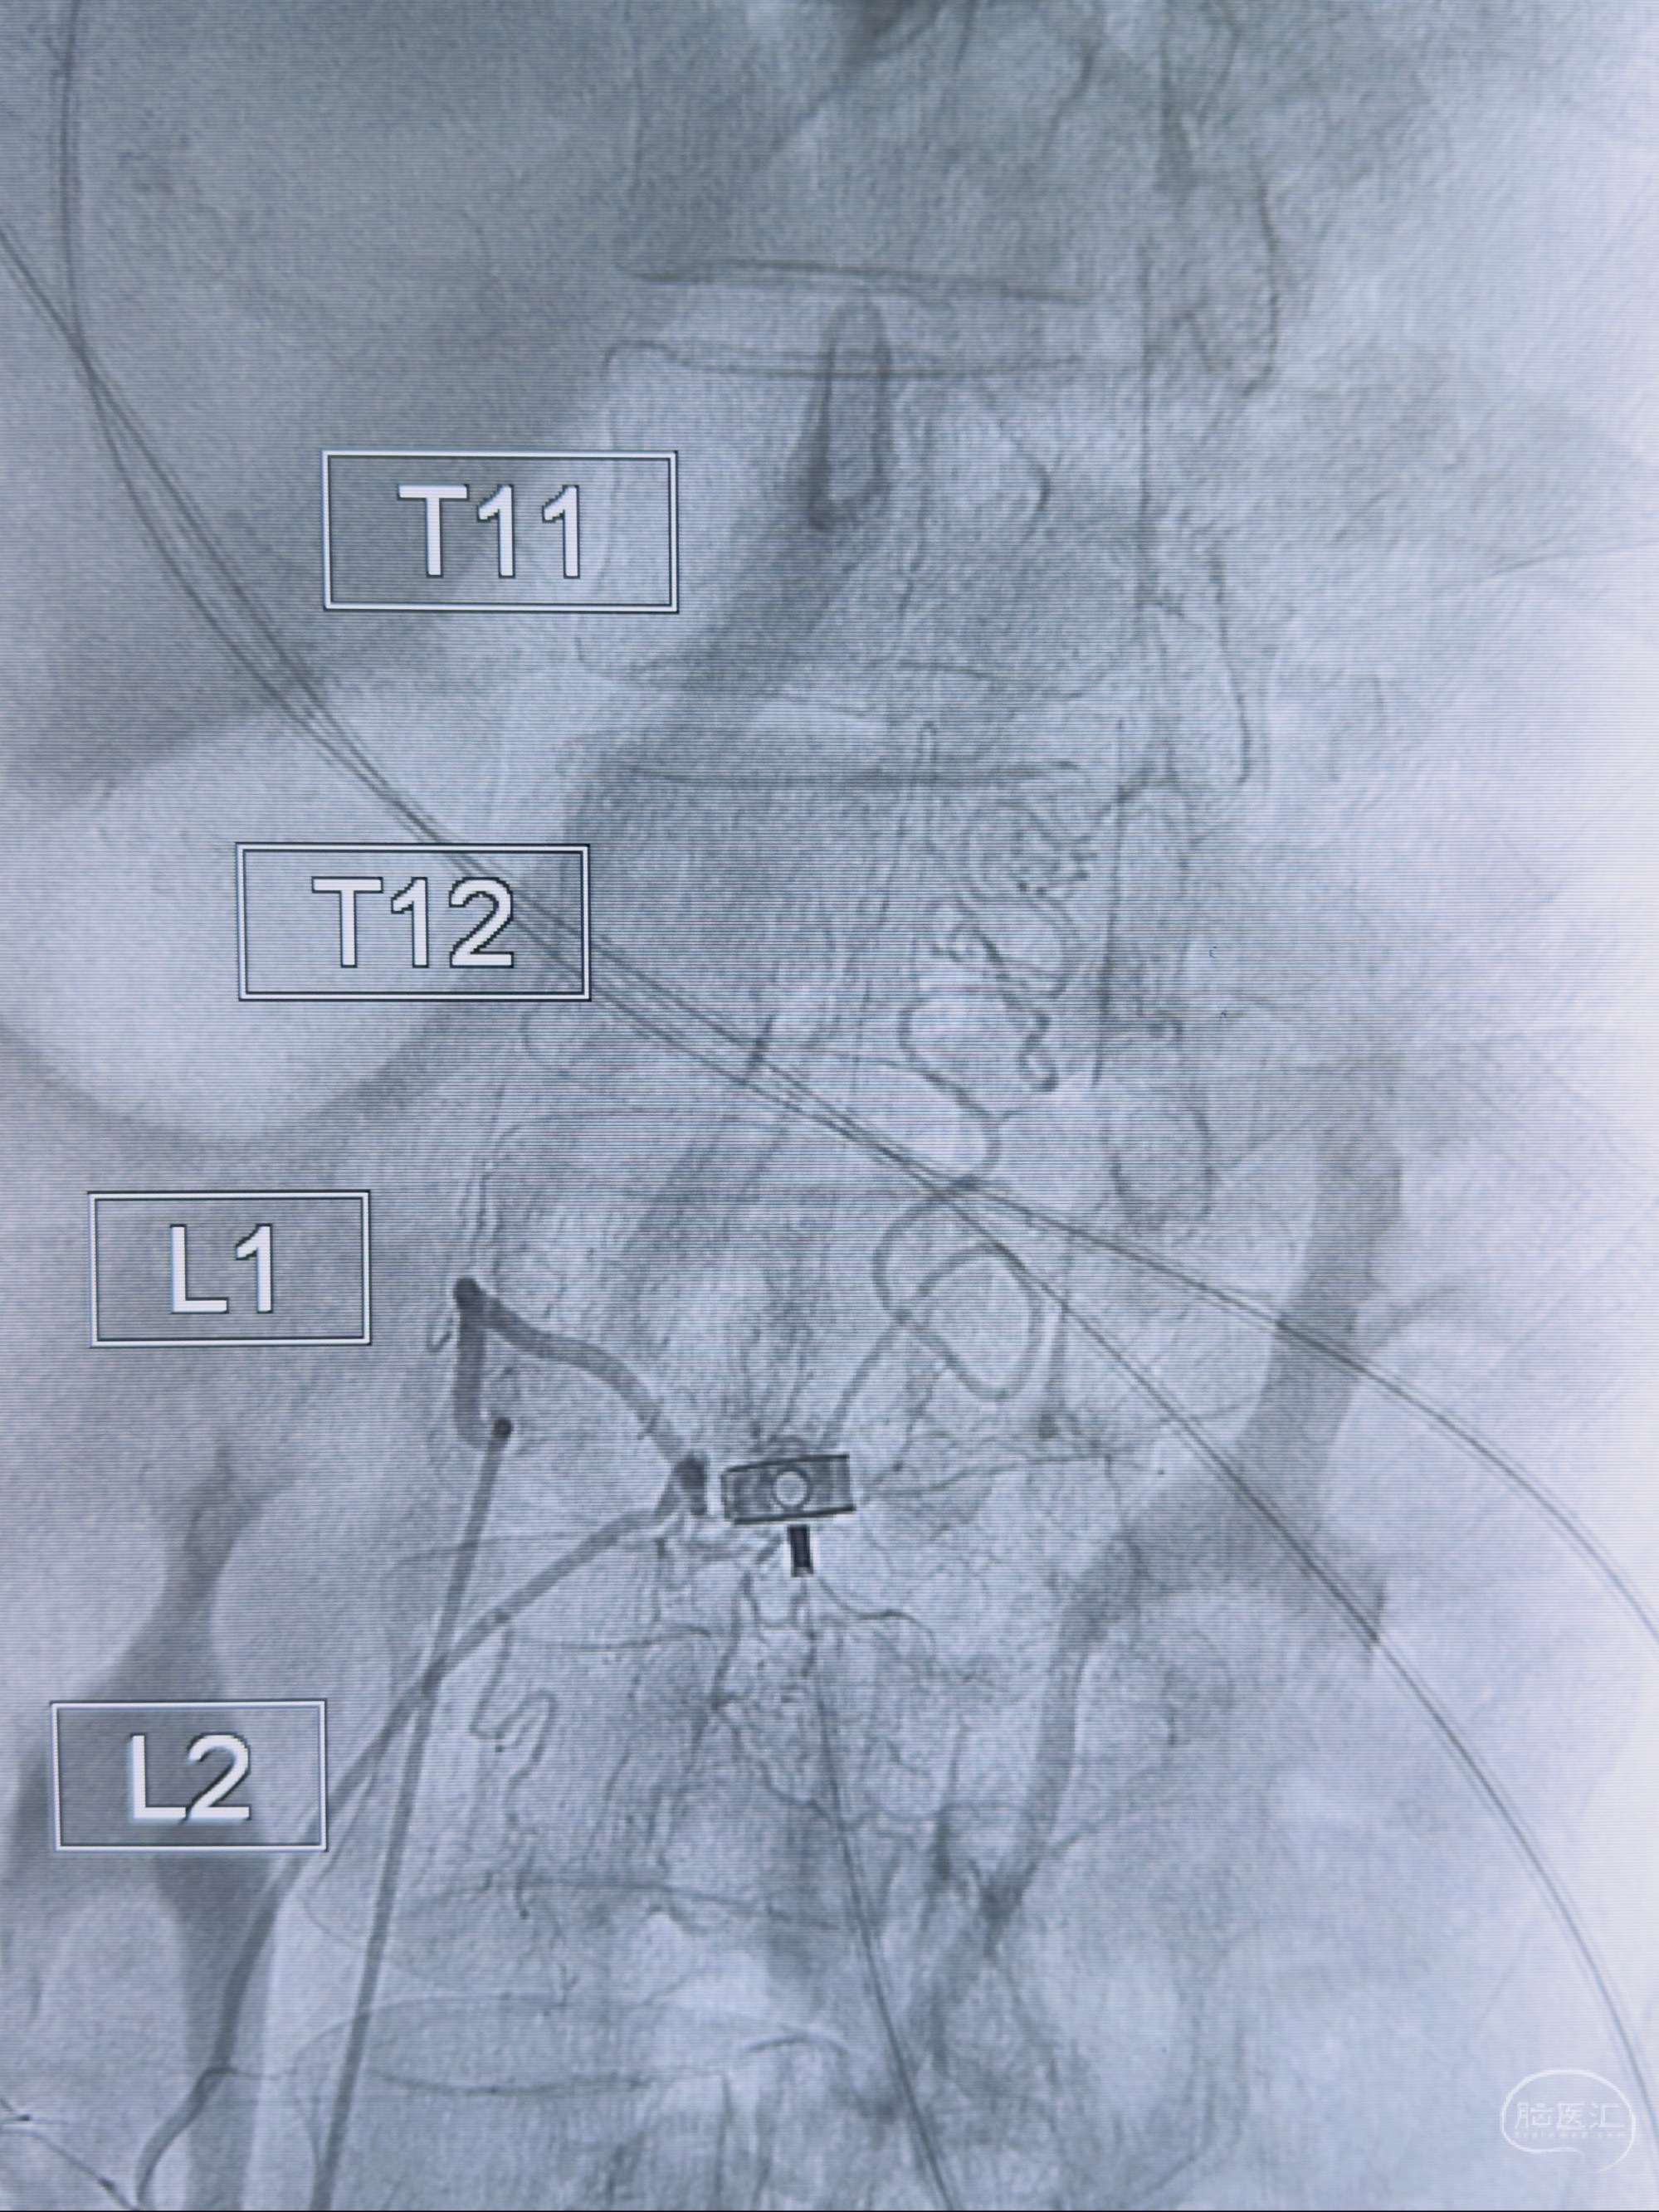

2023-10-13DSA:右侧L1水平硬脊膜动静脉瘘,供血动脉为右侧L1,附近动脉未见明确吻合供血,供血动脉处可见脊髓前动脉发出

1.建议外科手术,已行美兰定位c